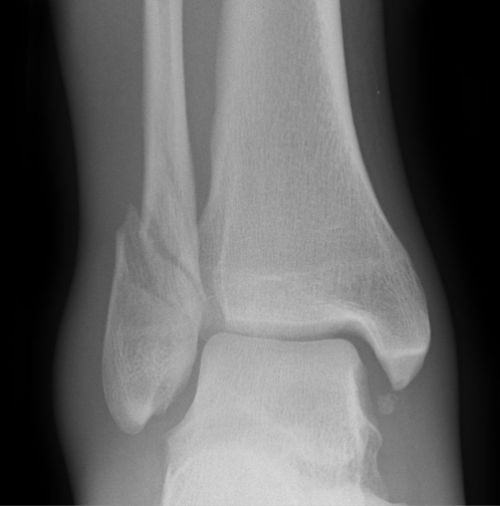

Hva slags fraktur er dette?

Weber B.

distal extent at the level of the talar dome; may extend some distance proximally

usually spiral

tibiofibular syndesmosis usually intact, but widening of the distal tibiofibular joint (especially on stressed views) indicates syndesmotic injury

medial malleolus may be fractured

deltoid ligament may be torn, indicated by widening of the space between the medial malleolus and talar dome

variable stability, dependent on the status of medial structures (malleolus/deltoid ligament) and syndesmosis; may require ORIF

Weber B fractures could be further subclassified as 9

B1: isolated

B2: associated with a medial lesion (malleolus or ligament)

B3: associated with a medial lesion and fracture of posterolateral tibia